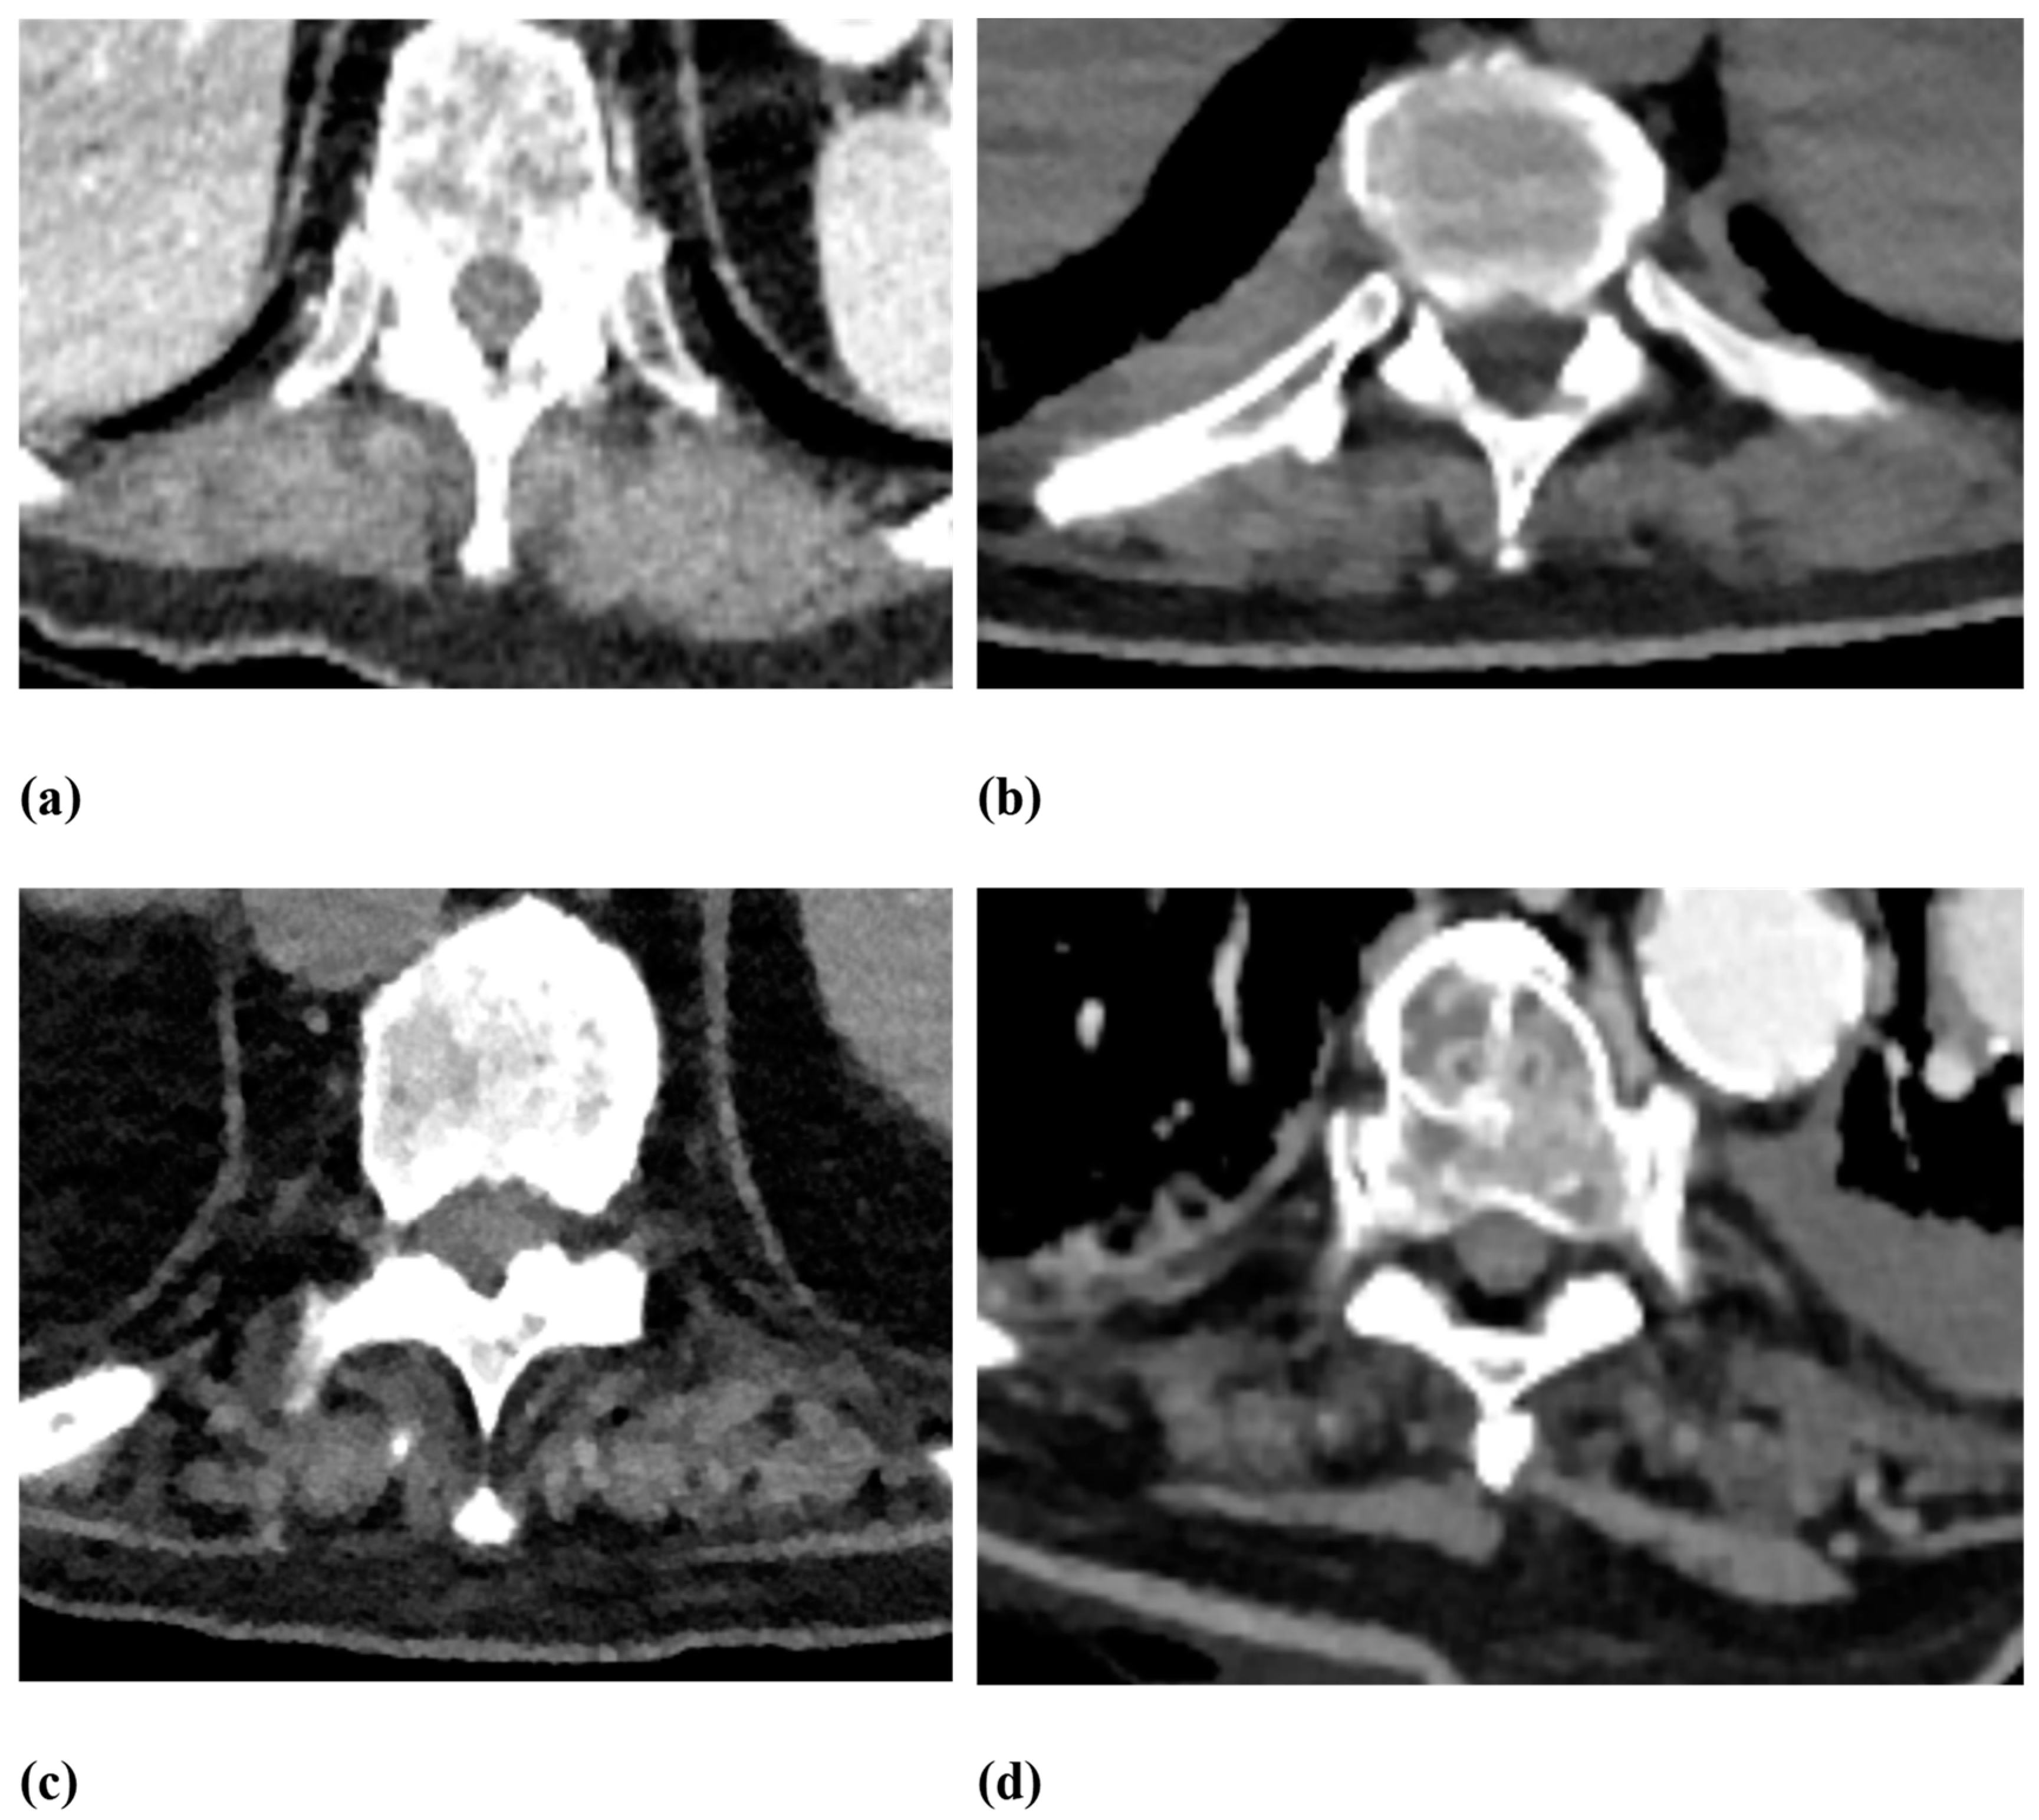

2.2. Image Analysis

| Fatty degeneration of the autochthonous back muscles | Goutallier score 0–4:

|